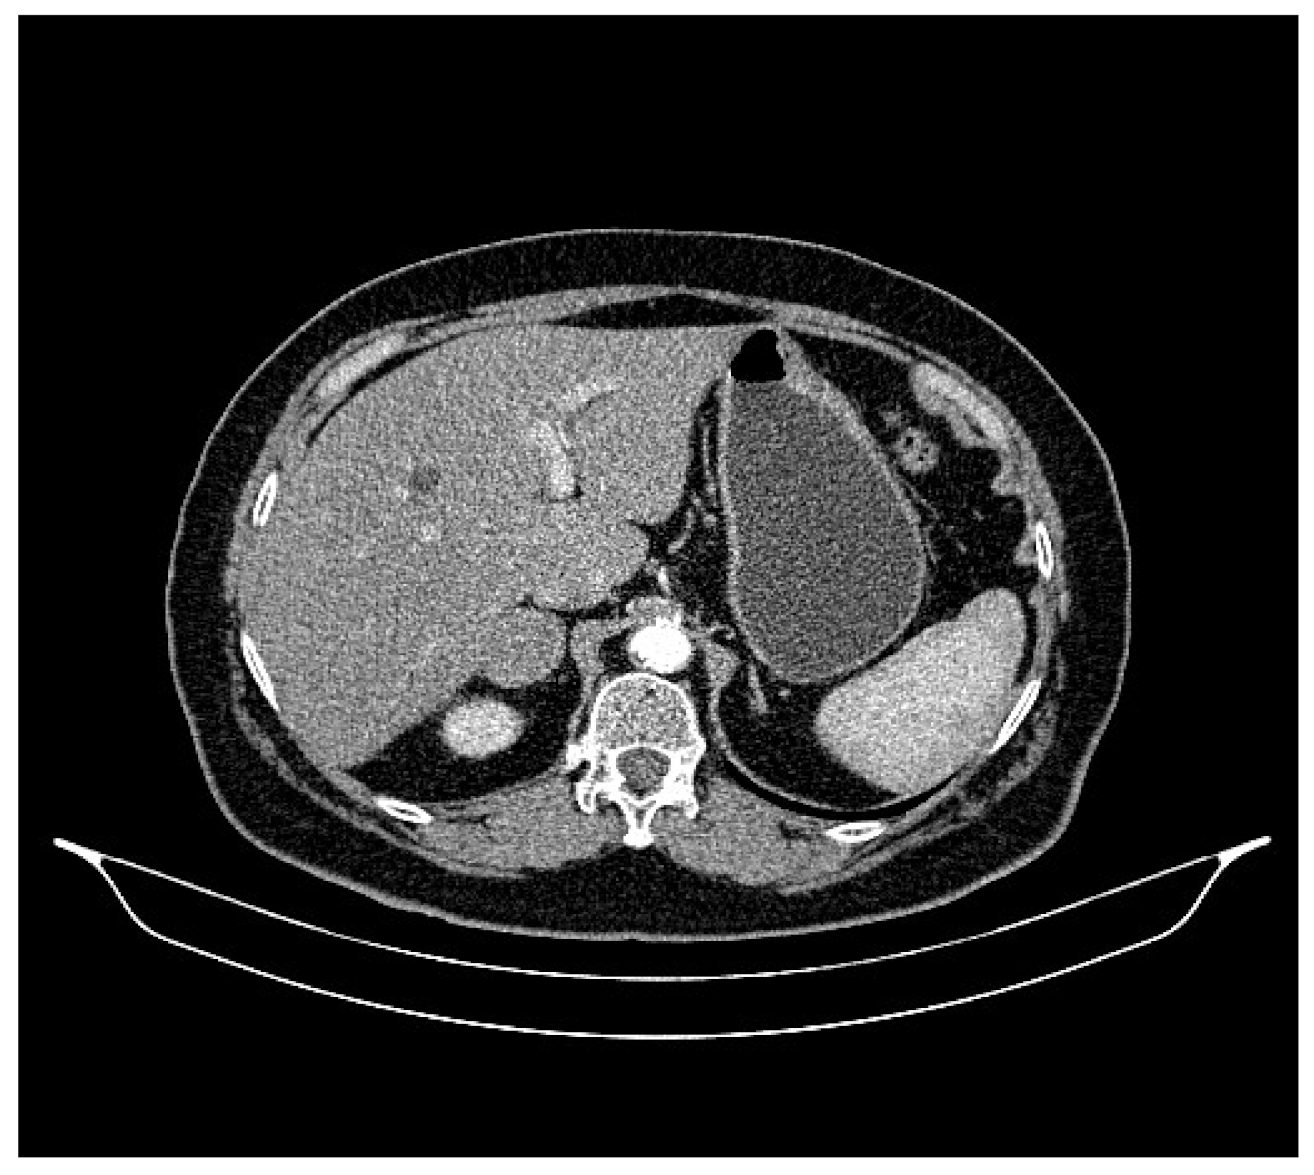

2. Case Presentation